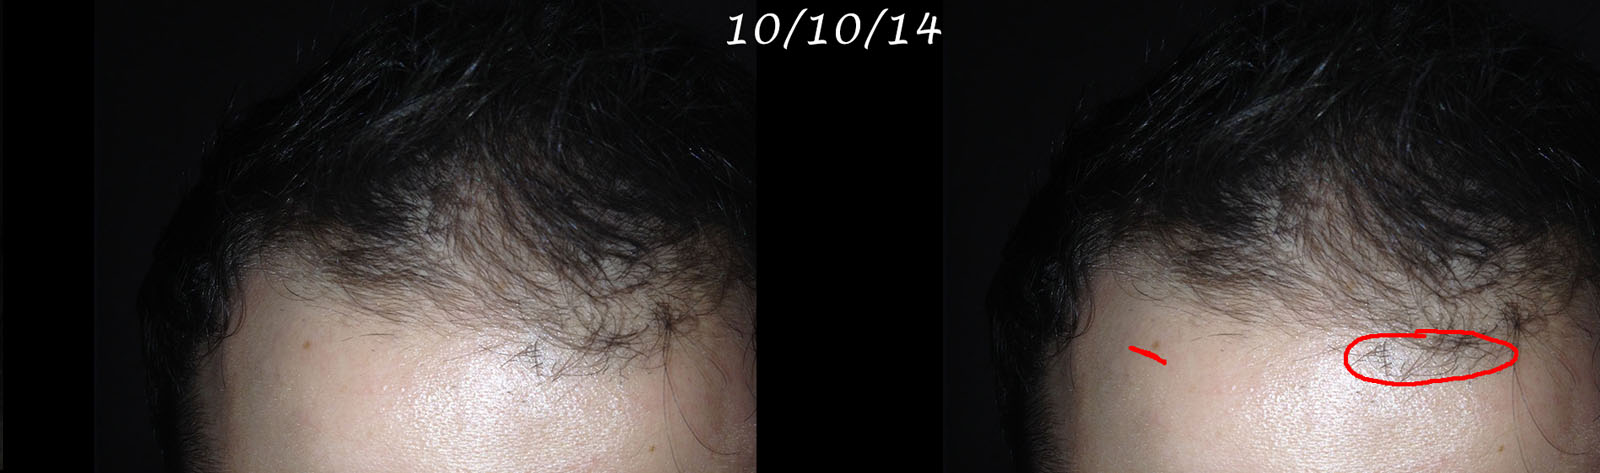

Here are pics taken May 27, 2014 a week before starting propecia and getting back on rogaine.

Here are pics taken May 27, 2014 a week before starting propecia and getting back on rogaine.